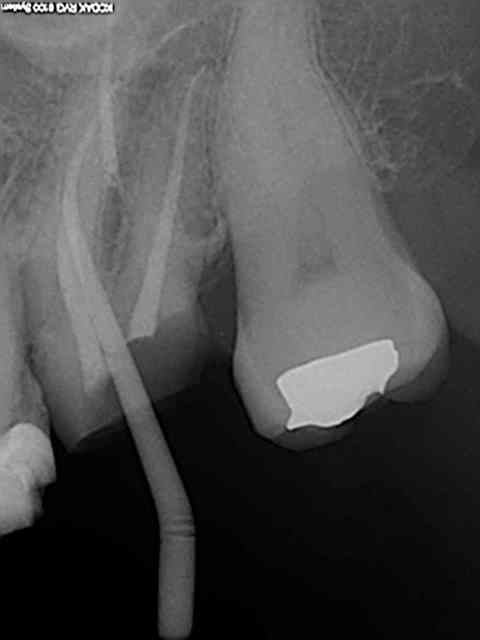

27/02/2014 à 18h03

MV2 à coté du canal palatin.

13/03/2014 à 17h35

45mn, pas de cathétérisme manuel, sx, s1, r25, endo activator, monocones scellés ( ciment : tubuli seal, sybro endo), pas de lentulo, pour 80 euros minimum syndical hein macho ?